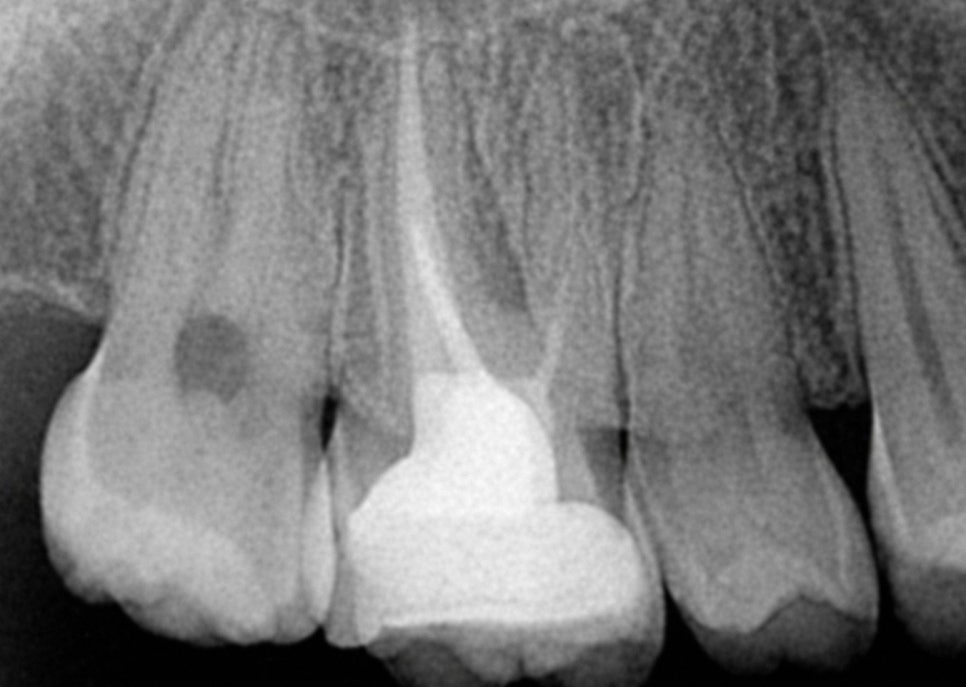

여기서 중요한 점은 처음 받을 때보다

더 까다로운 과정이라는 것이며

제일 먼저 국소마취 후

기존에 들어있던 충전재를

모두 제거해야 됩니다.

단단하게 굳어있는 재료를

조심스럽게 제거하면서

치질은 손상시키면 안 되기 때문에

이 과정이 생각보다 복잡합니다.

제일 중요한 것은

최종 보철물을 꼭 씌우는 것으로

치수 조직을 제거한 곳은

영양 공급이 안 되면서 약해집니다.

크라운을 씌우지 않으면

씹는 힘을 버티지 못해 파절될 수 있으므로